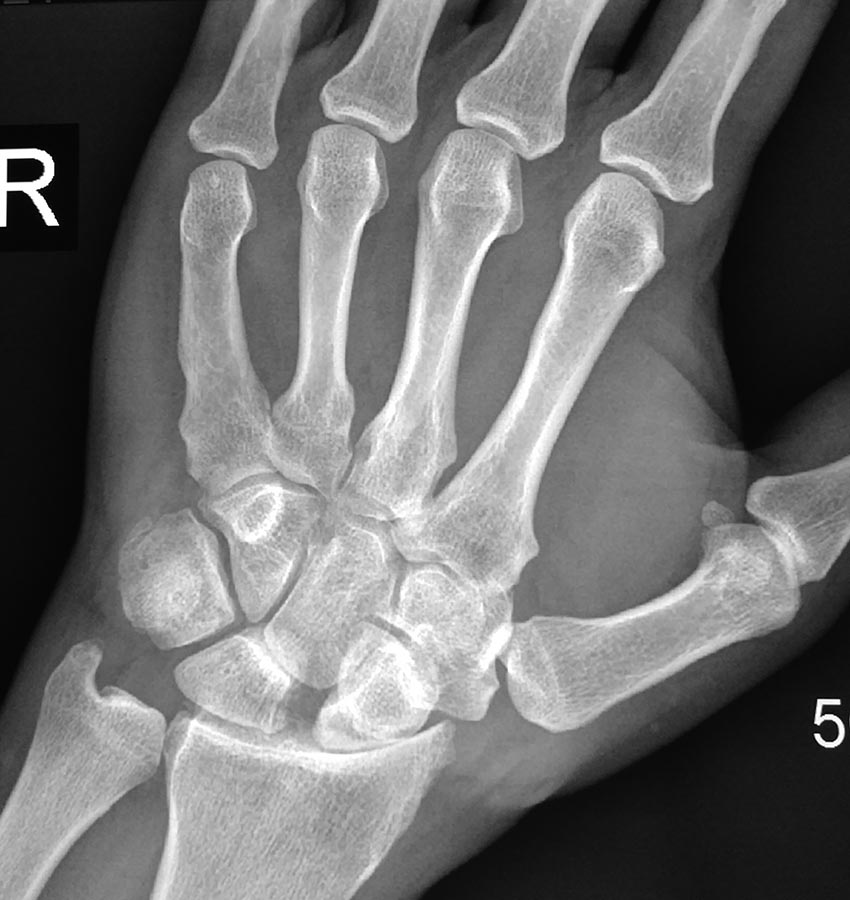

Больной С 42 года,обратился с жалобами на боли л/з суставе,усиление боли

при осевой и ротационной нагрузках. травма около 2-х лет назад,лечился

самостоятельно. При осмотре:отек л/з сустава,ограничение разгибания и

сгибания.При пальпации усиления боли в проекции ладьи,иррадиация боли по

ходу лучевого нерва. Ваше мнение по тактике лечения?